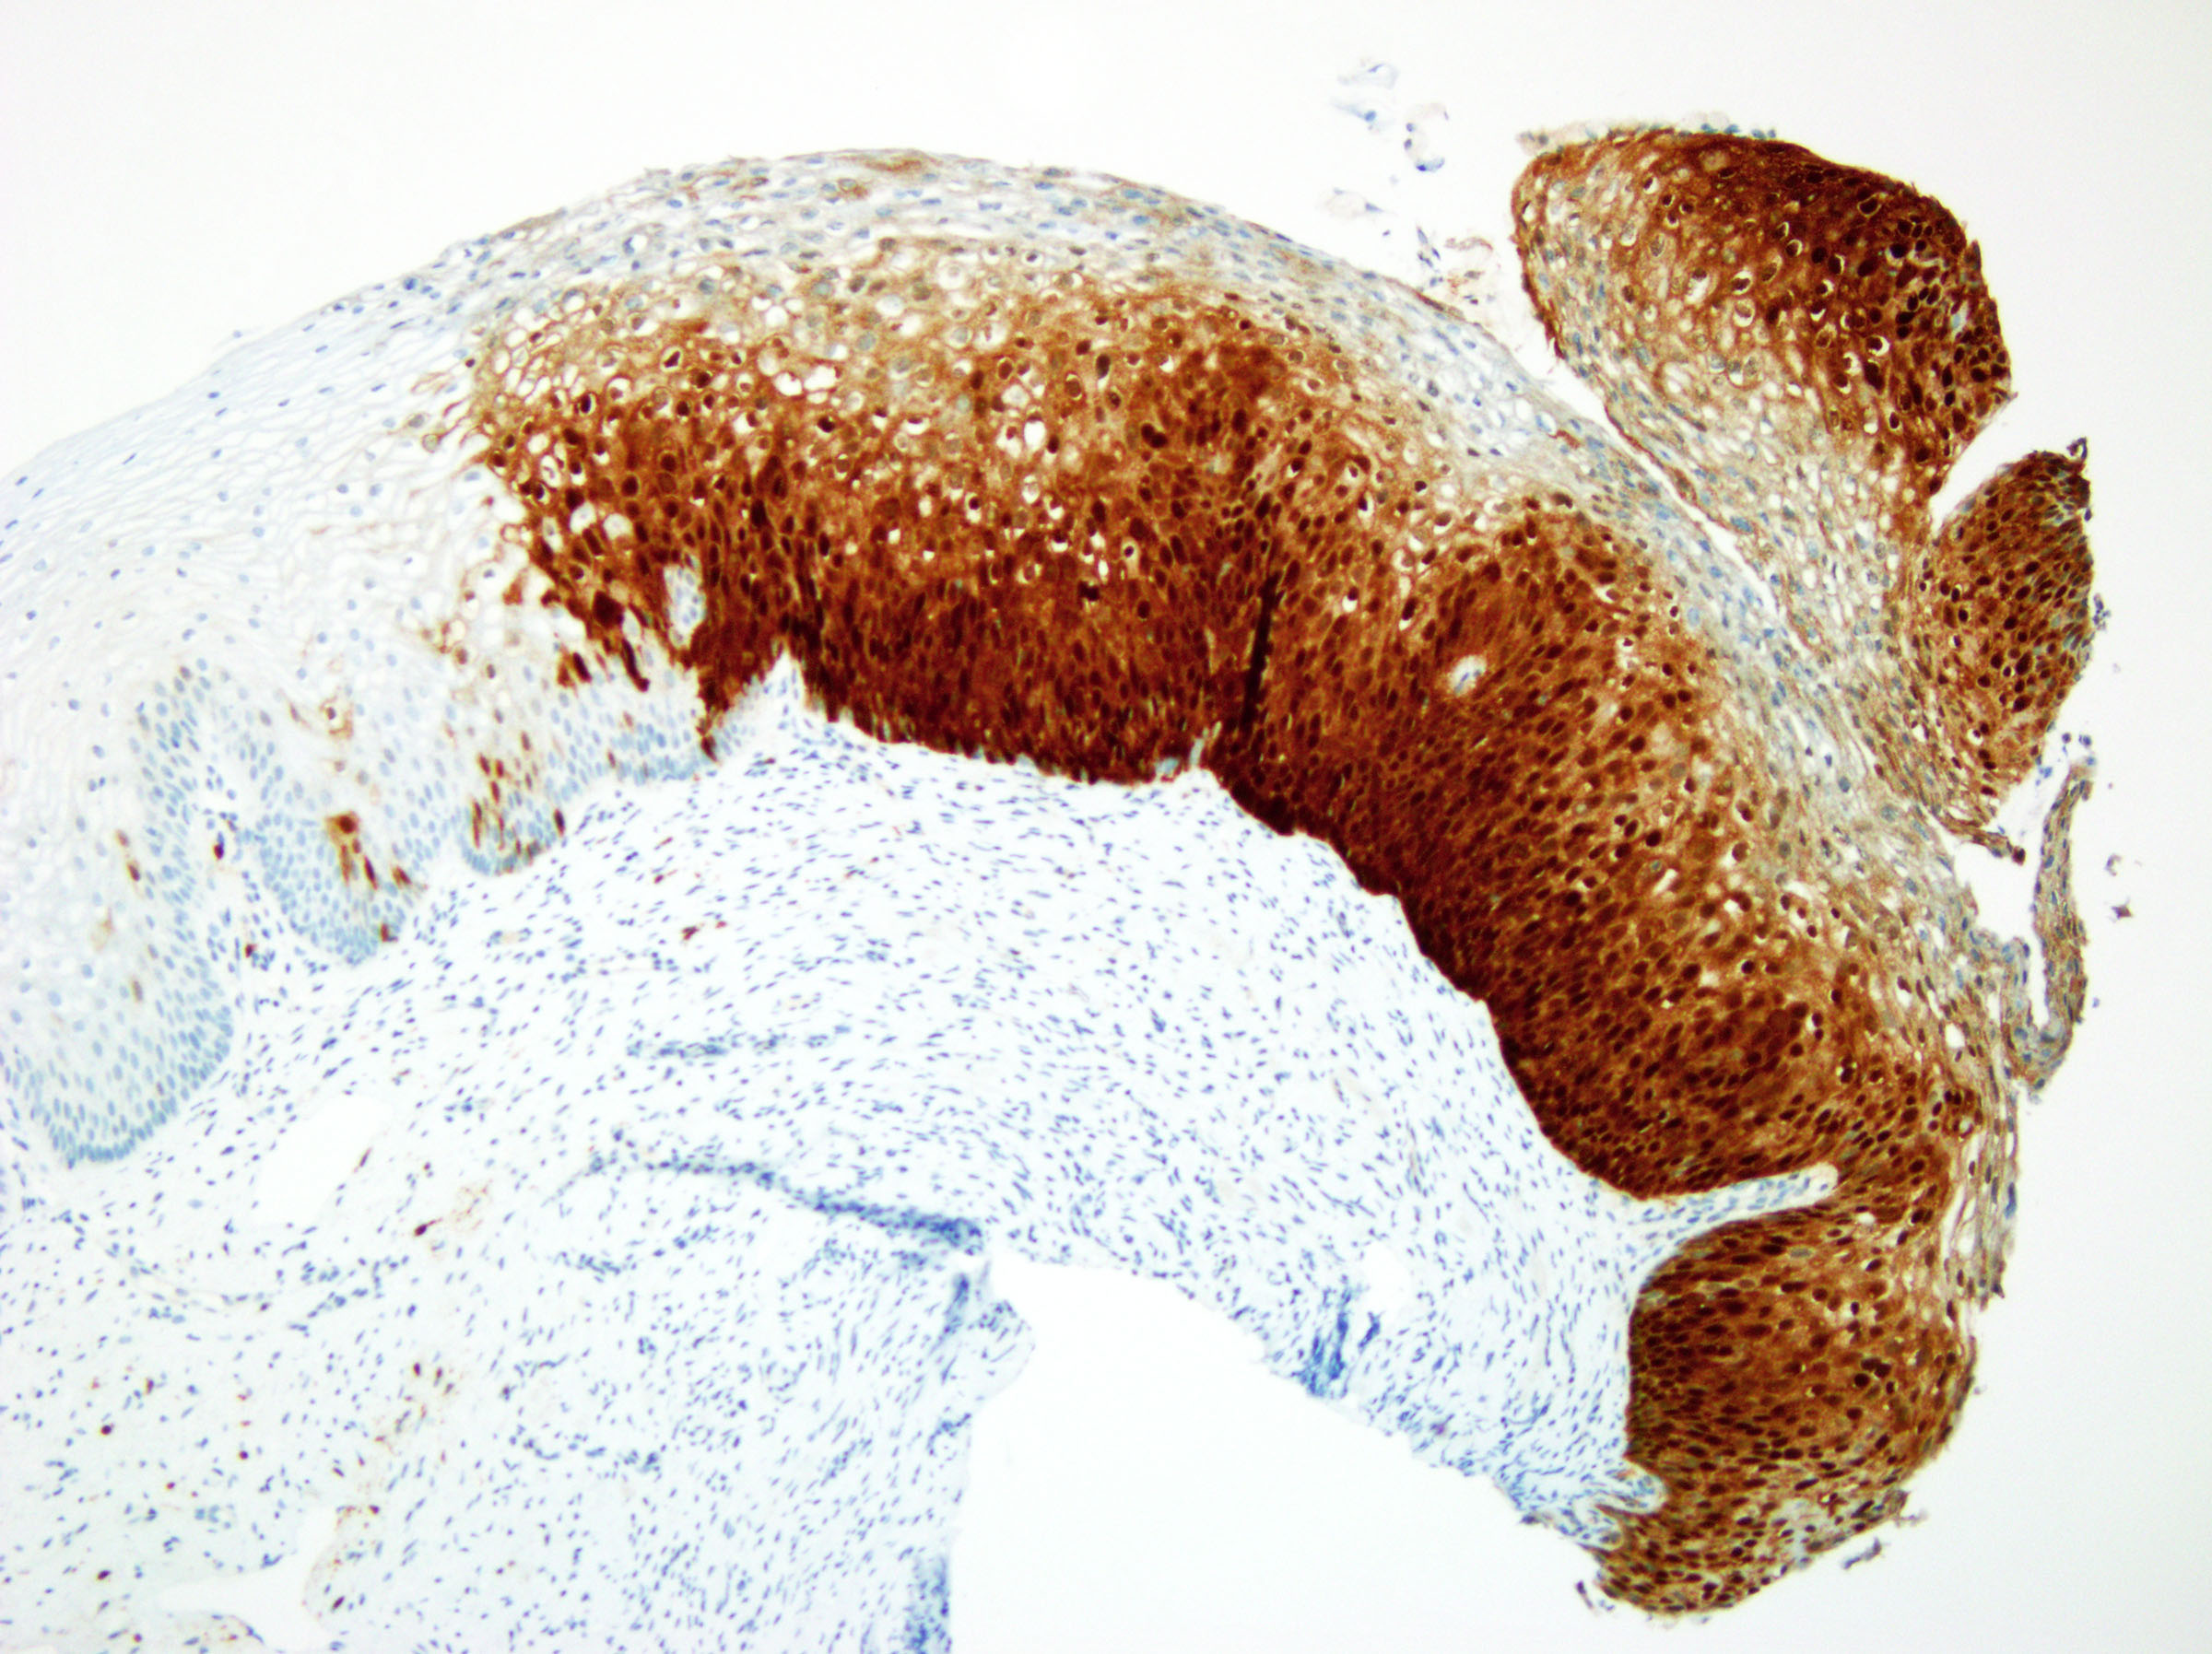

ベンタナ OptiView CINtec p16(E6H4) トレーニングプログラムベンタナ OptiView CINtec p16(E6H4) を用いた婦人科がんにおける免疫染色の判定について学んでいただけます